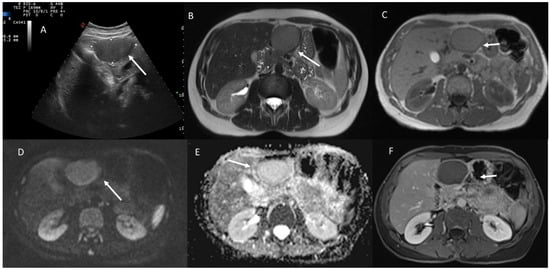

- Granata, V.; Fusco, R.M.; Catalano, O.; Filice, S.; Avallone, A.; Piccirillo, M.; Leongito, M.; Palaia, R.; Grassi, R.; Izzo, F.; et al. Uncommon neoplasms of the biliary tract: Radiological findings. Br. J. Radiol. 2017, 90, 20160561. [Google Scholar] [CrossRef] [PubMed]